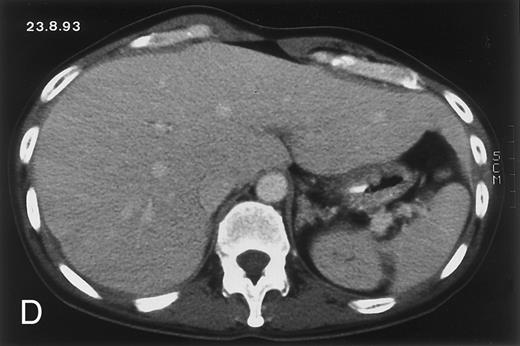

(D) On August 23, 15 days after the neutrophil count had dropped below 500/μL in the third chemotherapy cycle, focal liver lesions clearly decreased in size and number. (E) On September 30, 35 days after neutrophil recovery, multiple hepatic abscesses are seen (arrowhead). To show maximal extent of lesions the scan shown is at a slightly different level. (F) On June 16, 1994, 230 days after neutrophil recovery, the CT scan has normalized.